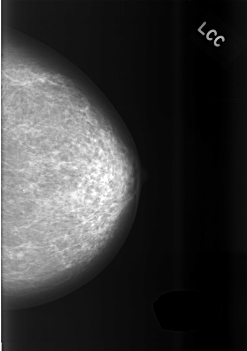

ics_version 1.0 filename C-0475-1 DATE_OF_STUDY 2 10 1995 PATIENT_AGE 66 FILM FILM_TYPE REGULAR DENSITY 2 DATE_DIGITIZED 10 2 1999 DIGITIZER LUMISYS LASER SEQUENCE LEFT_CC LINES 5616 PIXELS_PER_LINE 3944 BITS_PER_PIXEL 12 RESOLUTION 50 NON_OVERLAY LEFT_MLO LINES 5696 PIXELS_PER_LINE 4064 BITS_PER_PIXEL 12 RESOLUTION 50 NON_OVERLAY RIGHT_CC LINES 5728 PIXELS_PER_LINE 3936 BITS_PER_PIXEL 12 RESOLUTION 50 OVERLAY RIGHT_MLO LINES 5720 PIXELS_PER_LINE 4040 BITS_PER_PIXEL 12 RESOLUTION 50 OVERLAY |